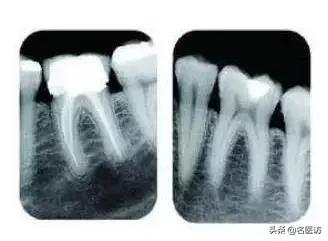

常见的牙科放射检查包括曲面体层片( 全景片 )、小牙片、头颅正侧位片、全头颅 CT、锥形束 CT( CBCT )等。由于牙齿下部隐藏在牙槽骨中,口腔医生要了解牙齿的整体情况就需要拍摄全景片;

要了解个别牙根及周围变化,则选择拍摄小牙片。医生要判断牙槽骨是否符合种植条件,或者了解埋伏阻生齿的三维位置以及其他颌骨内病变组织的形态大小时,则需要进一步拍摄 CBCT 。